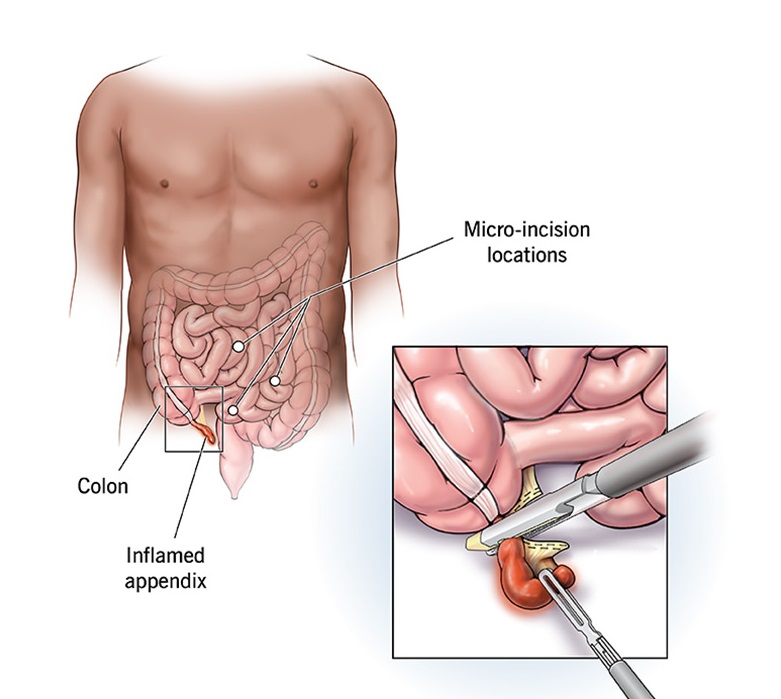

Overview

Package includes:

Days in hospital : 2 to 3 Days (For patient and one attendant)

Days in hotel : 7 Days (For patient and one attendant)

Room type in hospital : Shared

Room type in hotel : Private

Hotel category: Standard

Value added benefits of the Open - Appendicectomy:

Ø Doctor consultation charges

Ø Lab tests and diagnostic charges

Ø Room charges inside hospital during the procedure

Ø Surgeon Fee

Ø Nursing charges

Ø Hospital surgery suite charges

Ø Anesthesia charges

Ø Routine medicines and routine consumables (bandages, dressings etc.)

Ø Food and Beverages inside hospital stay for patient and one attendant.

Extra benefits:

ü Interpreter

ü Visa assistance

Ø Site tourism of the city

Ø Follow up with the doctor

Ø Airport pick up and drop

Ø Free online consultation with the doctor

Ø Priority appointments with the doctor

Ø Room upgrade from sharing to private